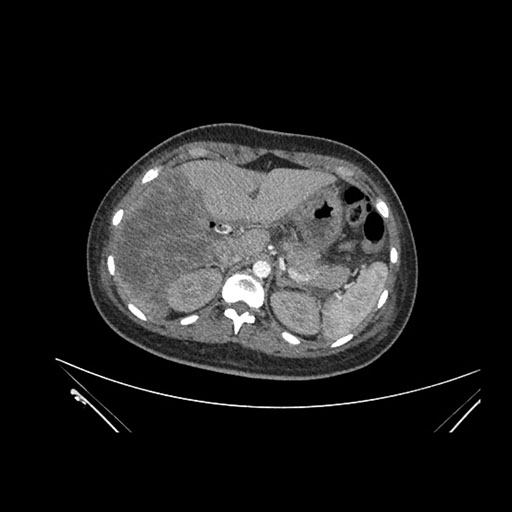

Imaging Analysis

Look through the patient's CT scan to identify any areas of concern for the necessary procedure.

Axial Arterial

Based on initial findings, which issue(s) would you be most concerned about?